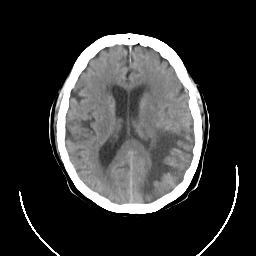

CT Study #3 -- Slice #16

[Home][Help][Clinical][Tour 1] Slice 16